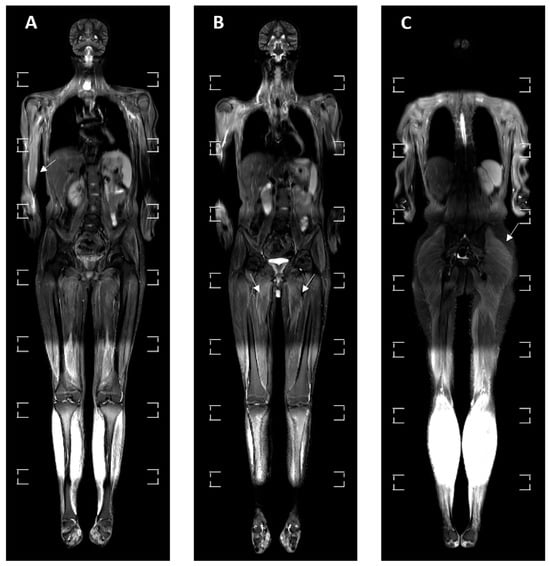

3.4. MRI Findings

| BME | 8 (24.24%) | 2 (22.22%) | 0 | 3 (42.86%) | 3 (30%) | p = 0.288 |

| Myositis | 10 (30.30%) | 1 (11.11%) | 6 (85.71%) | 1 (14.29%) | 2 (20%) | p = 0.004 * |

| Synovial fluid | 9 (27.27%) | 4 (44.44%) | 2 (28.57%) | 0 | 3 (30%) | p = 0.260 |

| Liver enlargement | 1 (3.03%) | 0 | 0 | 1 (14.29%) | 0 | p = 0.280 |

| Spleen enlargement | 3 (9.09%) | 0 | 0 | 1 (14.29%) | 2 (20%) | p = 0.352 |